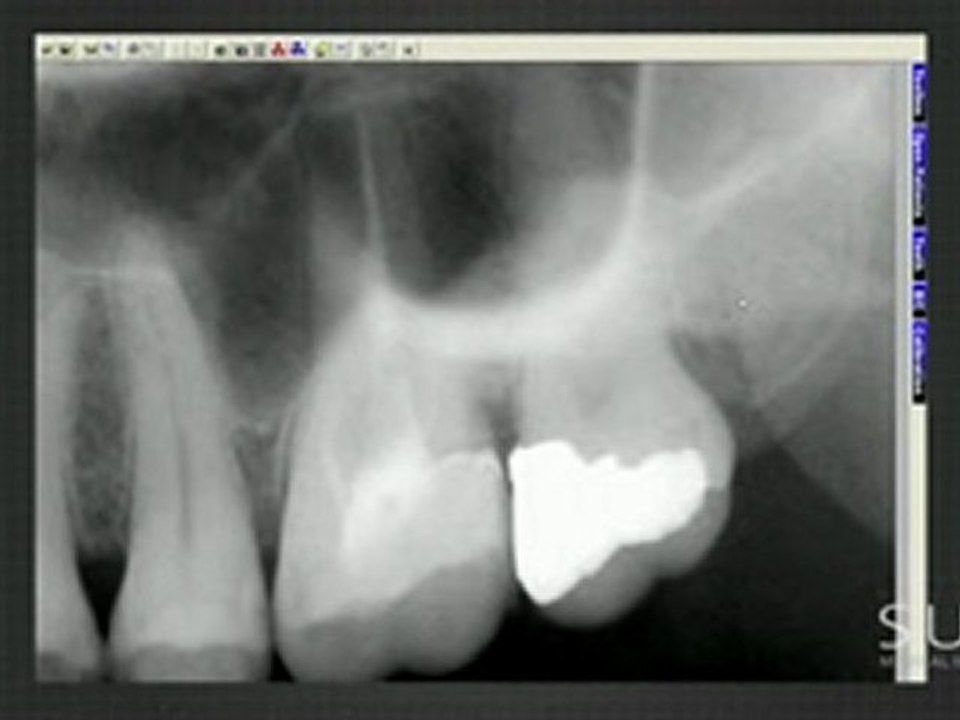

In case of tooth pain you'll be able to contact the appropriate tooth doctor associated 1st they're going to recommend you for an x-ray from that the problems may be determined. however you've got to pick out the correct tooth doctor and understand the treatments they supply. The dental digital x rays provide the foremost distinctive approach of scratching over the pc screen then on. <br /><br />Visit @ http://sotaimaging.net